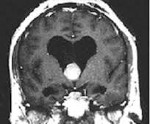

На снимках компьютерной томографии коллоидная киста выглядит круглым образованием белесого цвета, которое располагается в полости III желудочка мозга, имеющего на рентгенограмме черный цвет. Окраска ткани кисты намного интенсивнее соседней ткани головного мозга, которая имеет на снимках сероватый оттенок.